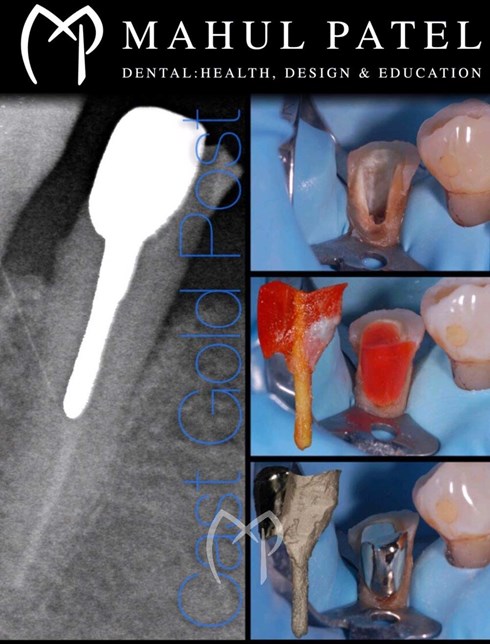

• Posts

• Crowns, Partial Crowns, Onlays and Bridges